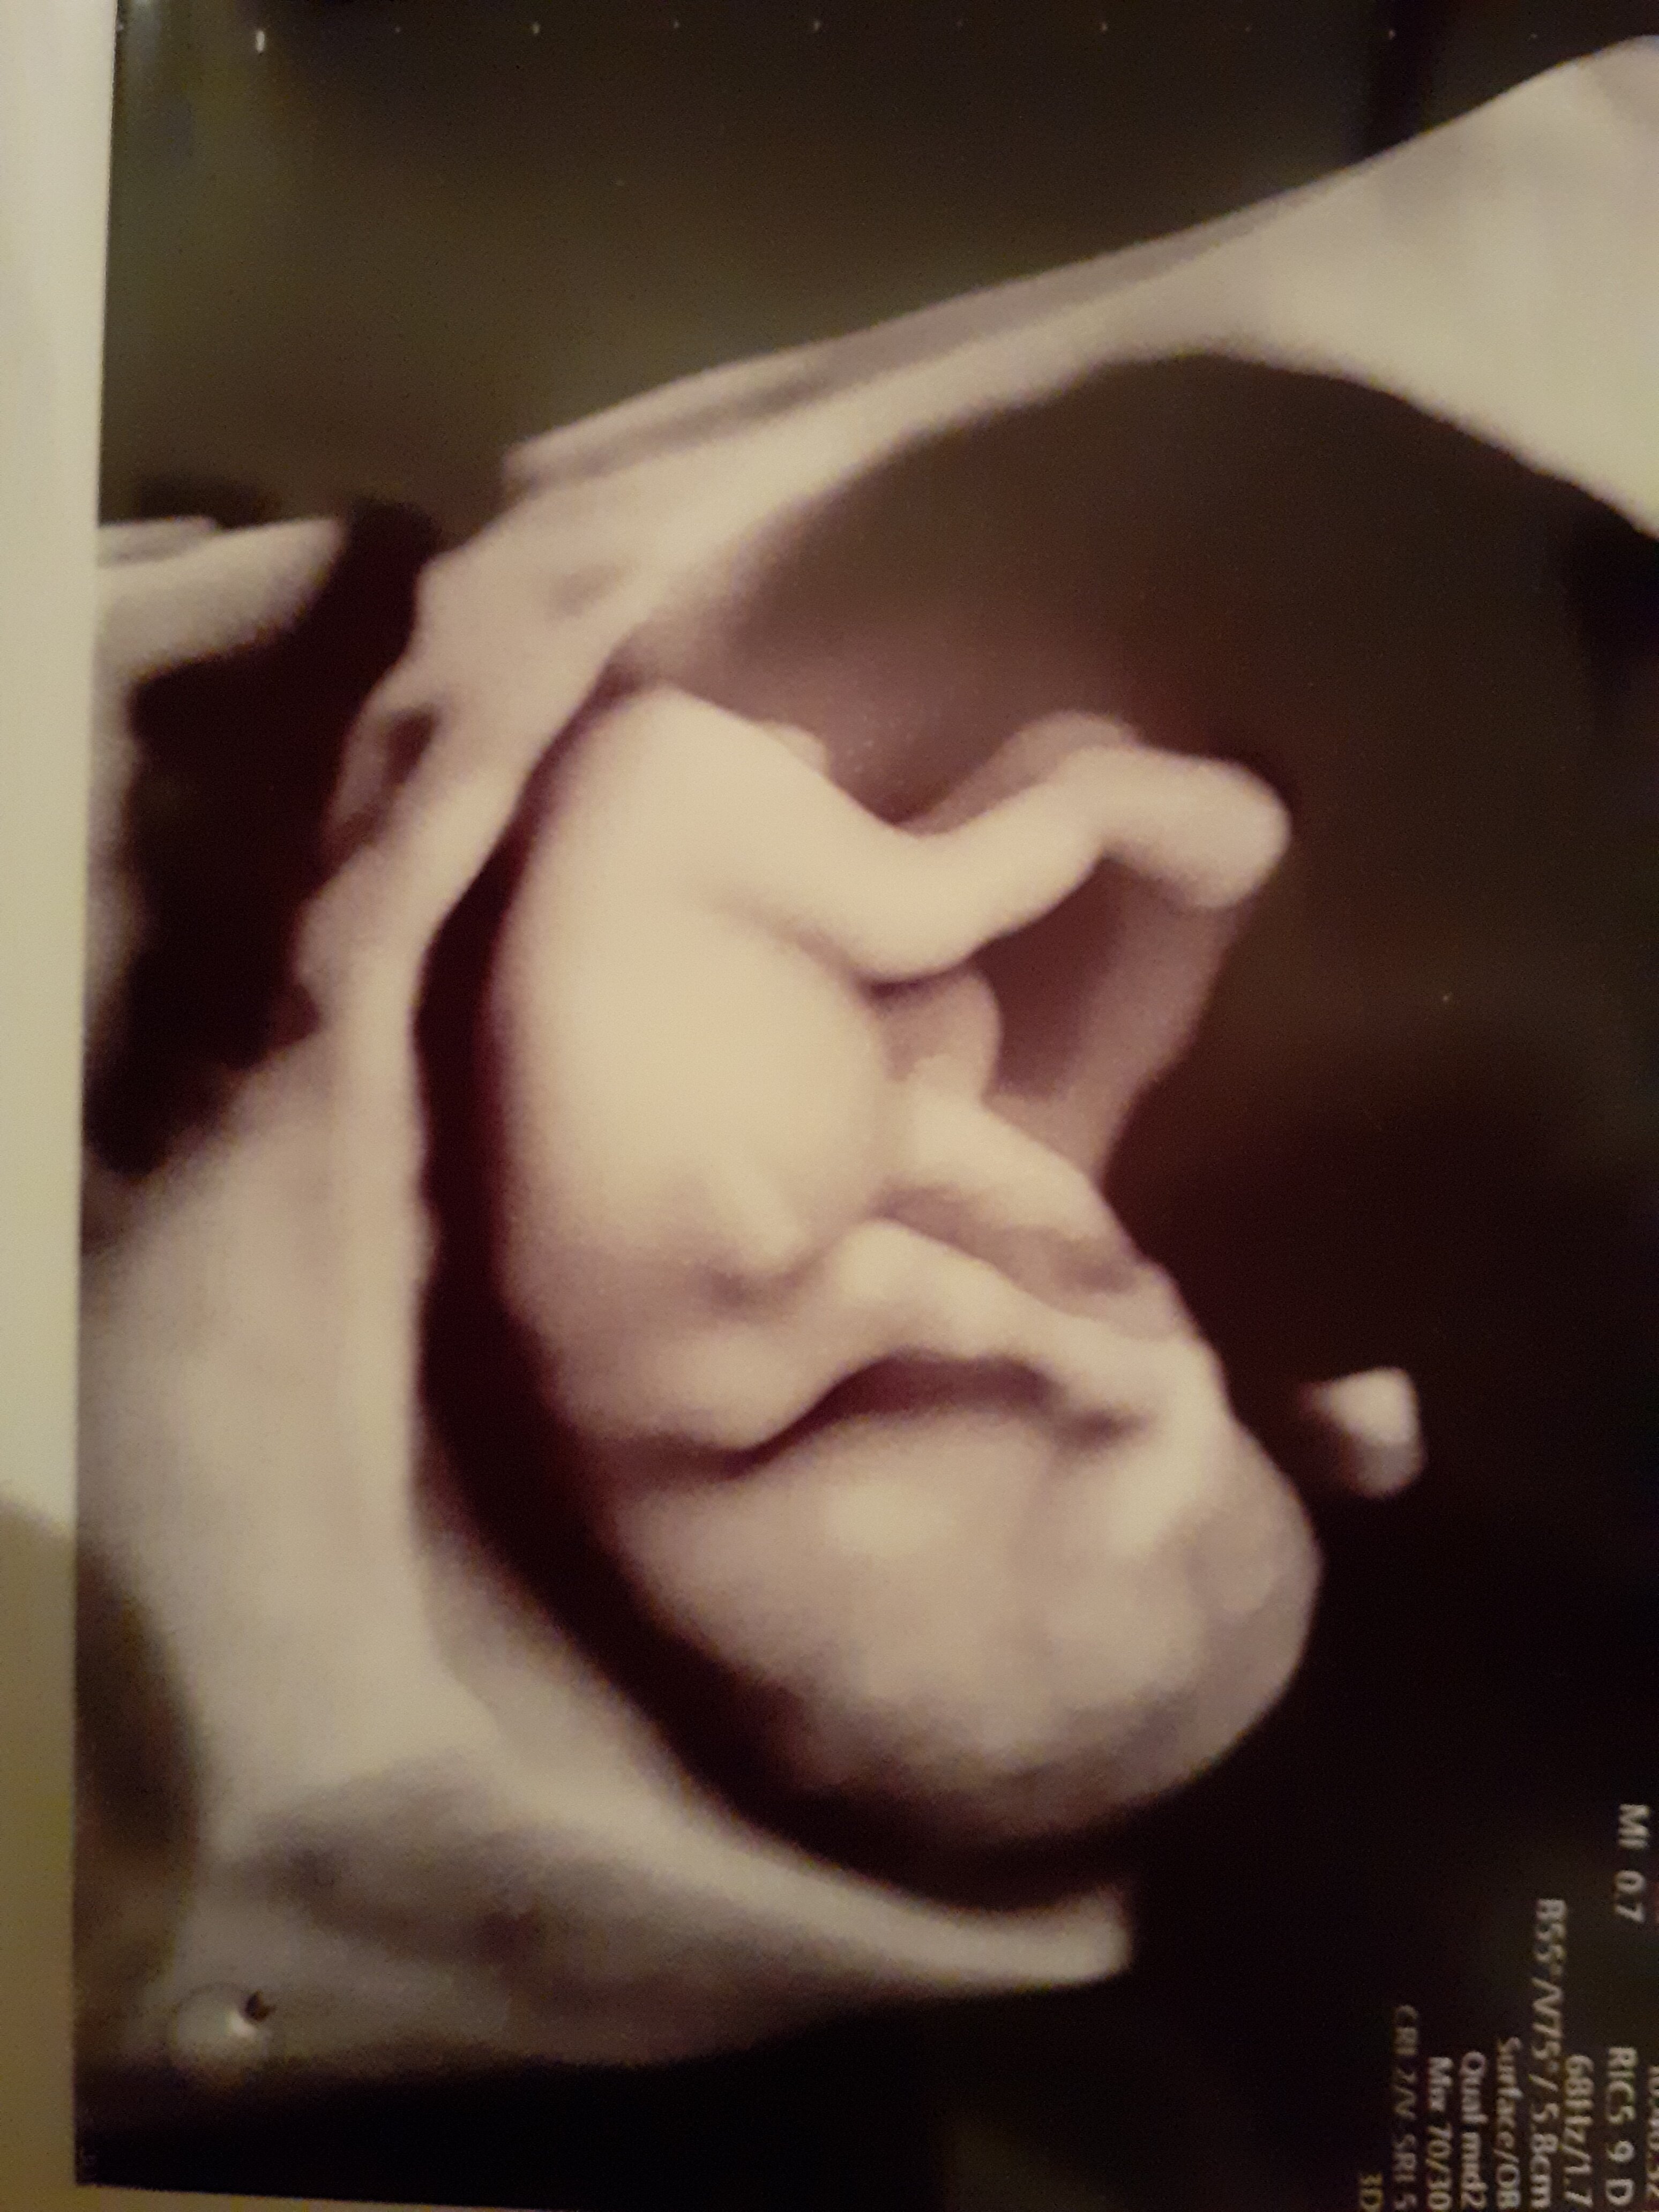

W każdym razie próbował przez brzuch, ale dziecko nie ułożyło się najlepiej, także miałam także dopochwowo. Wyniki wszystkie są dobre. Miałam testy pappa i ponoć po badaniach ultrasonograficznych ryzyko chorób jeszcze bardziej zmamlało. Widziałam jak się dziecko rusza, jego kręgi, serduszko... Puścił też doktor, żeby posłuchać.

Pytałam także o płeć. Powiedział, że to za wcześnie jeszcze, żeby powiedzieć, ale na 90% to będzie chłopiec. Nie wiem, czy może sprzęt nie jest jakiś starszy, bo wiem, że niektórzy lekarze już podają płeć przy okazji tych badań, ale muszę powiedzieć, że po ostatnich przejściach z innymi lekarzami nie mam ochoty szukać nigdzie innego.